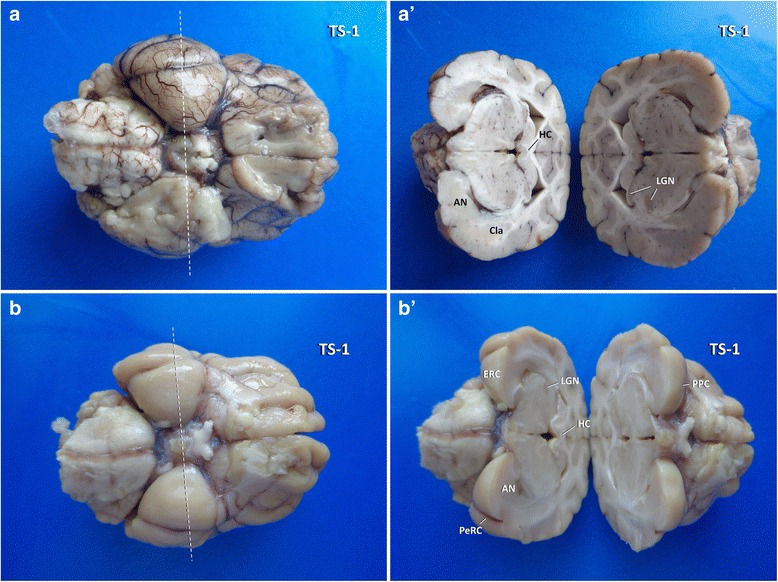

Fig. 4.

Insights into the three-dimensional orientation of the hippocampus after TS-1 (dashed line) in dog (a, a´) and cat (b, b′). AN: amygdaloid nucleus; Cla: claustrum; ERC: entorhinal cortex; HC: hippocampal commissure; LGN: lateral geniculate nucleus; PeRC: perirhinal cortex; PPC: pre-piriforme cortex